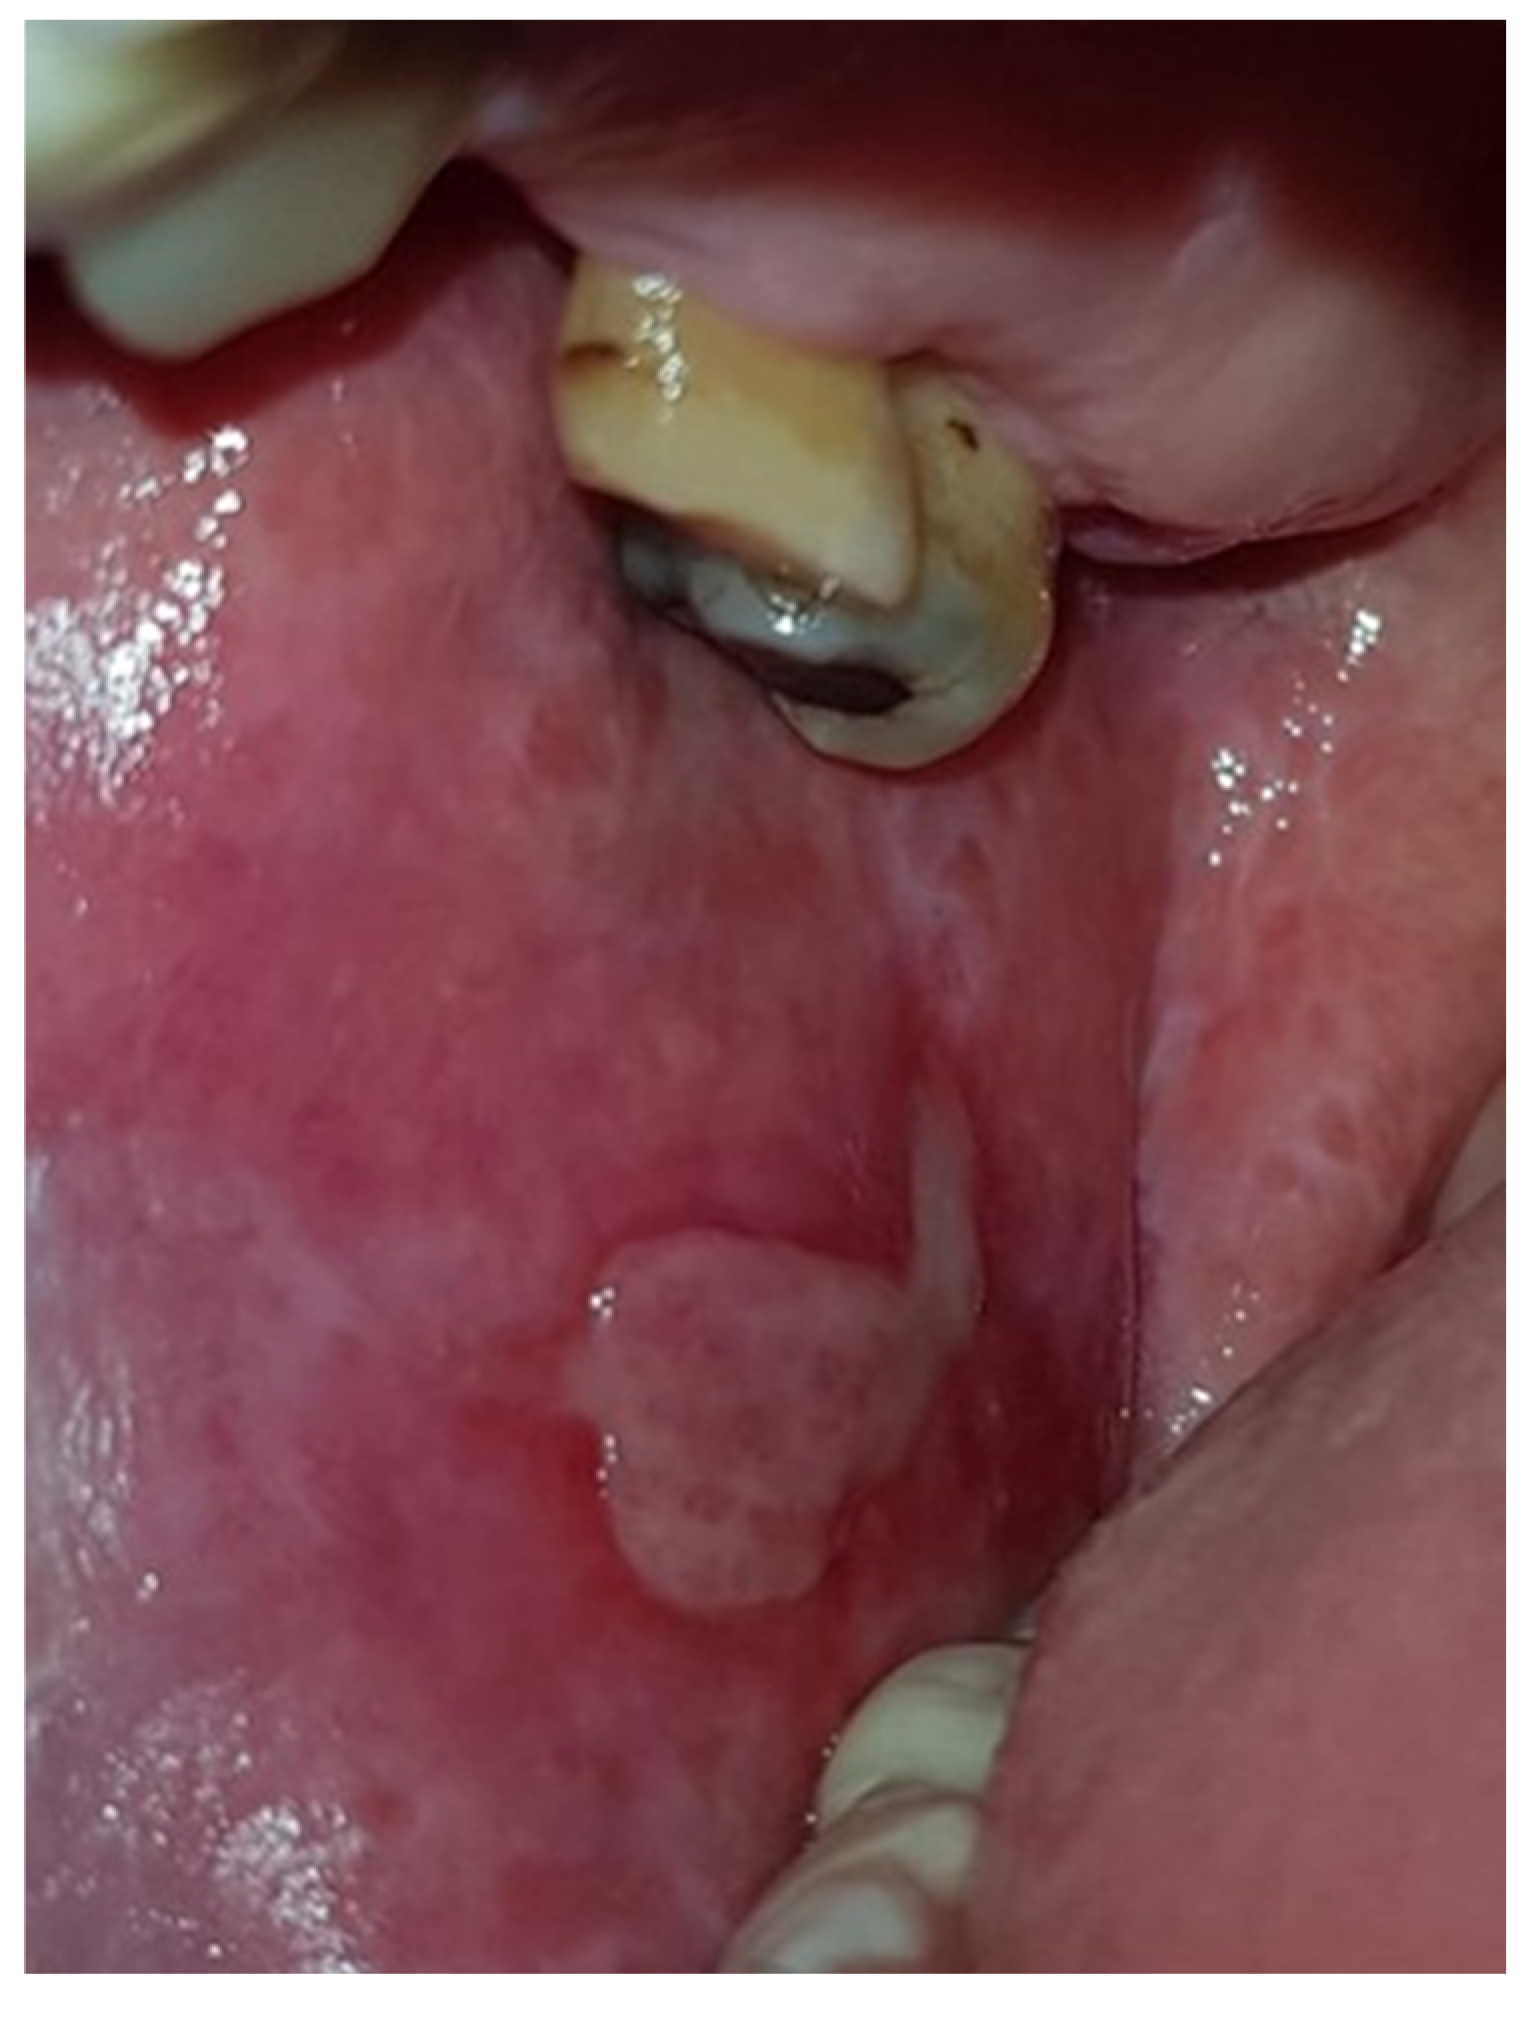

| Bullous/Erosive (Mixed) | 36 (19.4%) | 23 (17.7%) | 13 (23.2%) | 0.3838 | 8 (17.0%) | 28 (20.1%) | 0.6417 | 5 (16.7%) | 25 (19.1%) | 6 (24.0%) | 0.7825 |

| Atrophic | 13 (7.0%) | 11 (8.5%) | 2 (3.6%) | 0.2303 | 3 (6.4%) | 10 (7.2%) | 0.8526 | 1 (3.3%) | 10 (7.7%) | 2 (8.0%) | 0.6908 |